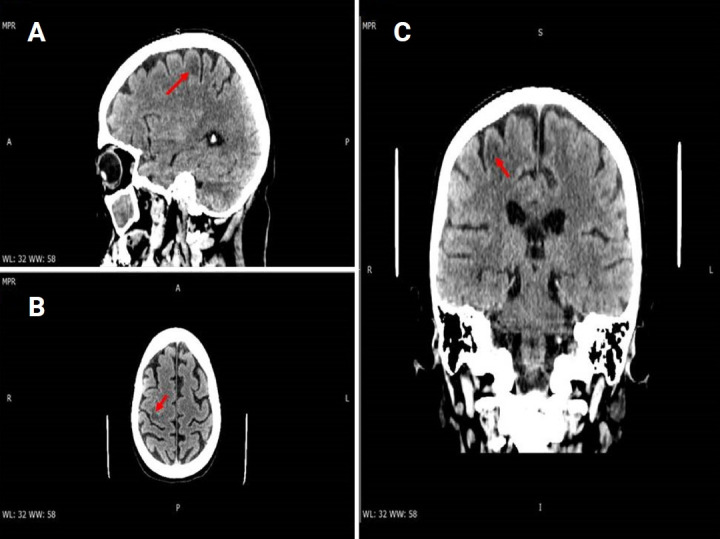

我们描述的情况下,一个47岁的妇女谁是困惑和抱怨左无力时,她提出了我们的机构。患者接受了头部计算机断层扫描,怀疑最近发生的缺血性发作(亚急性期)。患者住进神经内科,接受了磁共振成像(MRI)和造影剂治疗。临床和实验室结果以及MRI特征,特别是在敏感性加权成像(SWI)序列中出现低信号边缘,与进行性多灶性白质脑病(PML)的诊断一致。淋巴细胞减少导致免疫抑制,患者随后被诊断为先前未记载的艾滋病。我们的目的是在免疫功能低下的艾滋病患者中报道这一罕见的PML病例,描述其主要的MRI特征和SWI序列的可能作用。

We describe the case of a 47-year-old woman who was confused and complained about left-sided weakness when she presented to our institution. The patient underwent a head computed tomography that raised the suspicion of a recent-onset ischemic episode (subacute phase). The patient was admitted to the neurology department and underwent a magnetic resonance imaging (MRI) with contrast medium administration. The clinical and laboratory findings and the MRI features, particularly the presence of a hypointense rim in the susceptibility-weighted imaging (SWI) sequences, were consistent with a diagnosis of progressive multifocal leukoencephalopathy (PML). Immunosuppression was observed as a result of lymphopenia, and the patient was subsequently diagnosed with previously undocumented AIDS. Our aim is to present this rare case of PML in an immunocompromised patient with AIDS, describing the main MRI features and the possible role of SWI sequences.